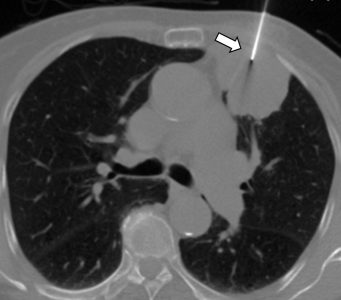

Ακτινολογία

Διαδερμικά κατευθυνόμενη βιοψία αδενοκαρκινώματος πνεύμονα